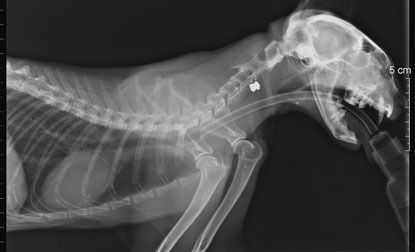

When our vets at the National Cat Adoption Centre in Sussex first saw Billy, he had so many puncture wounds they thought he’d been attacked by a wild animal. But as the treating Veterinary Officer recalls: “When we looked at his X-rays we could see his whole body and head were literally peppered with air gun pellets.”

Two pellets were removed from Billy’s neck but the rest, particularly the four lodged in his head, were just too deep. The Veterinary Officer said it was a “miracle” Billy had survived at all. Billy has been left totally blind in one eye and may only be able to see shadows with the other.